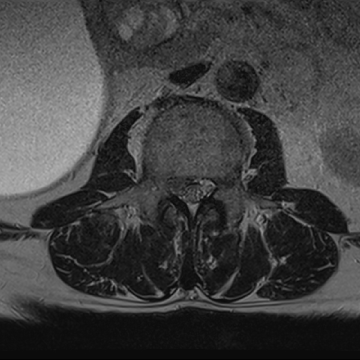

허리 디스크 수술 전·후

2022.08.01

2022.08.04

ㆍ환자 동의를 받은 자료이며, 이미지 사진은 실물과 다를 수 있습니다.

ㆍ모든 자료는 새움병원 자료입니다.